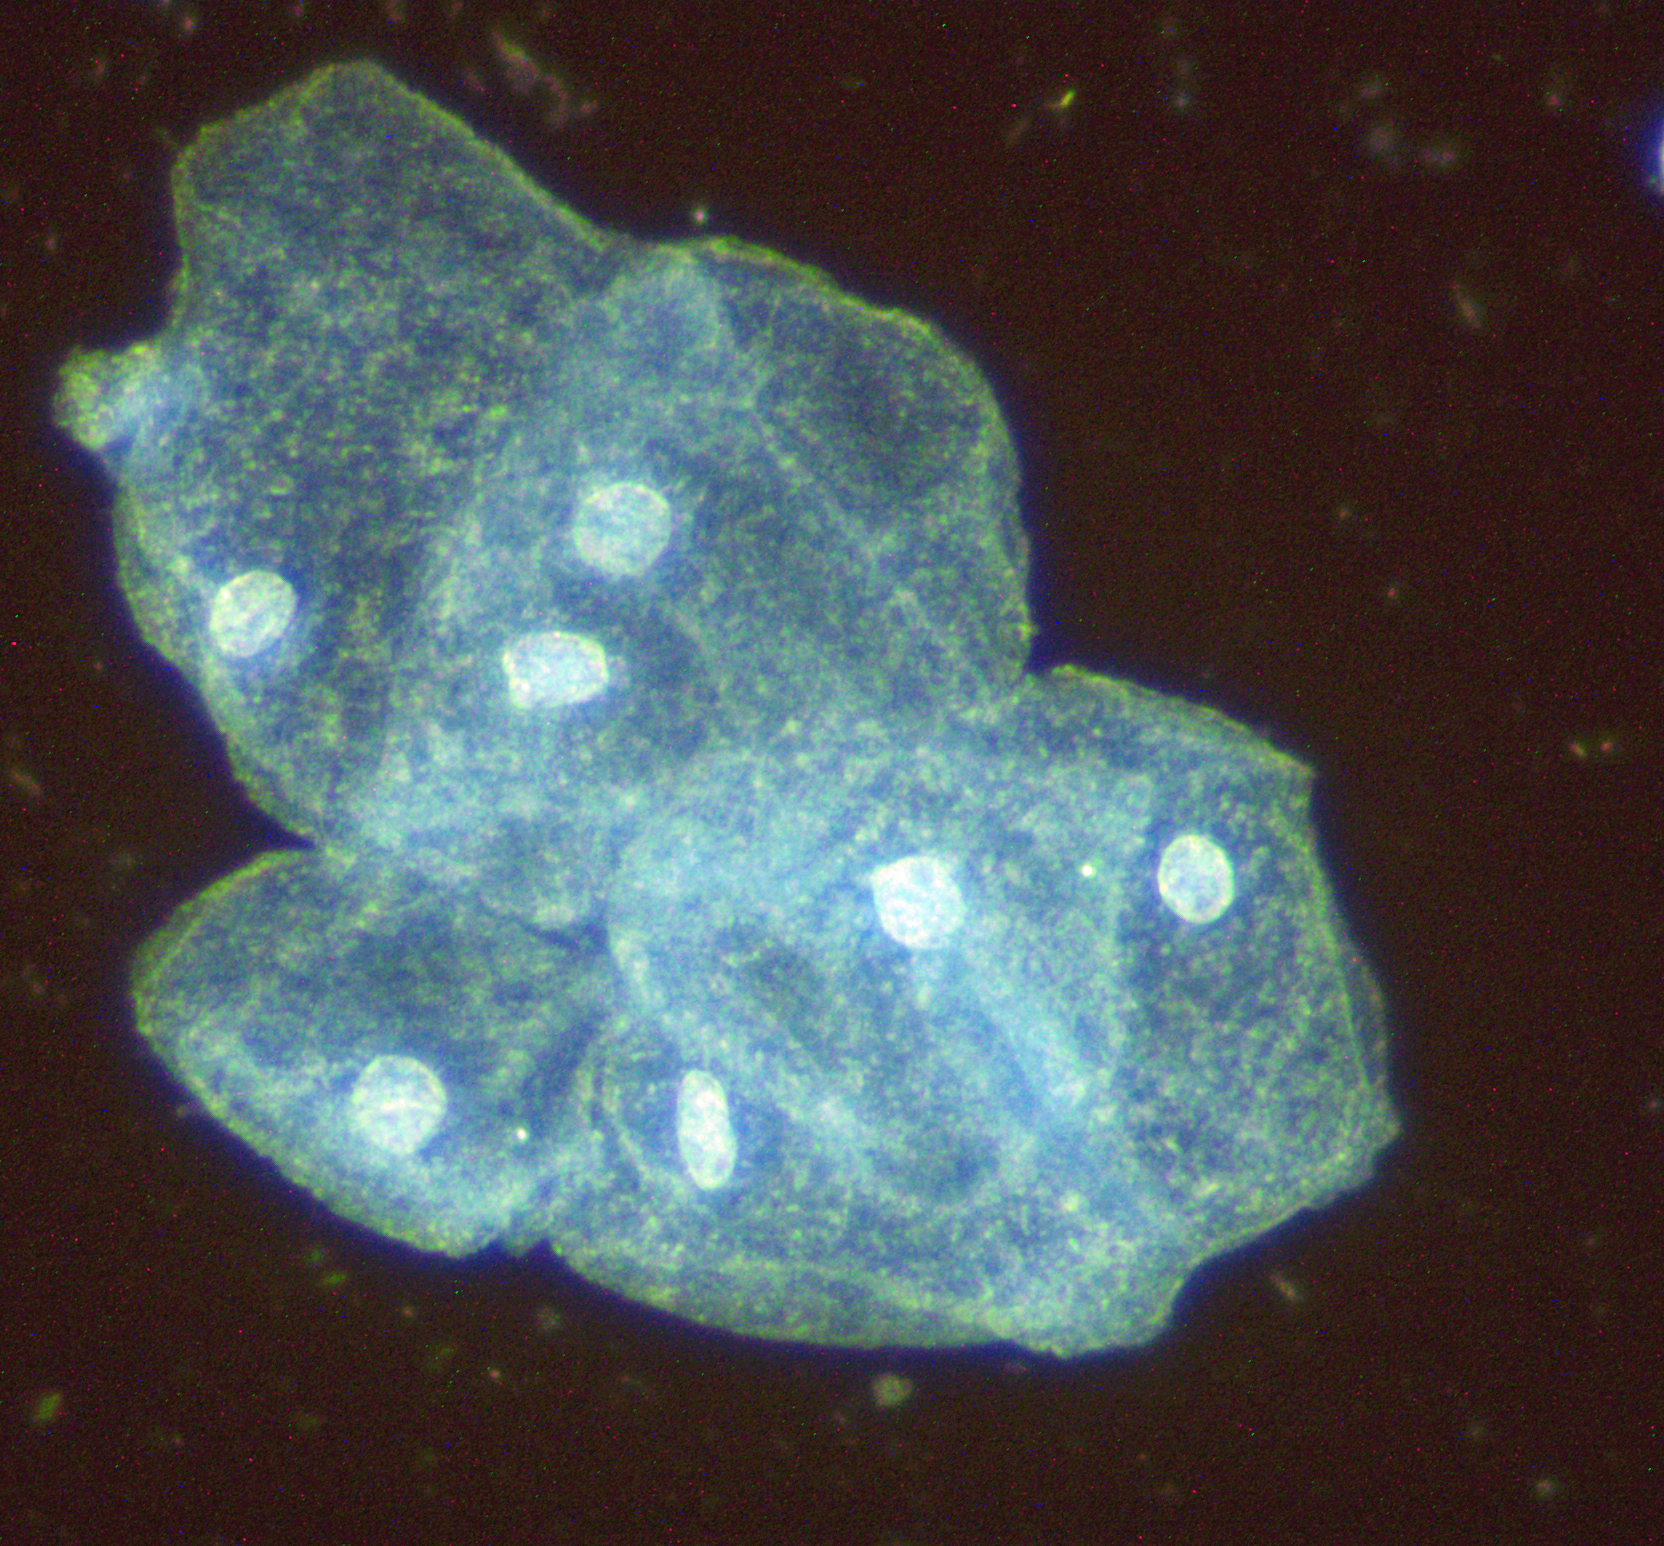

Epithelzelle Urin

Epithelzelle Urin

Epithelzelle im Urin unter dem Mikroskop im Dunkelfeld